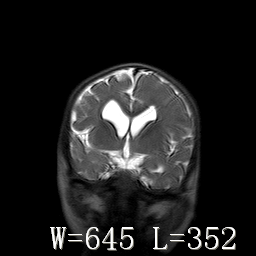

标题: PED3252:脑室增大。

女,3岁,3岁不会说话,阵发性抽搐、自伤。

考虑为梗阻性脑积水(中脑导水管狭窄)。

脑积水?脑发育不良?

侧脑室不规则,前后角尖角样,脑白质较少:考虑灰质发育不良可能

考虑,脑发育不良,胼胝体发育不全?(图片不全,矢状位?)